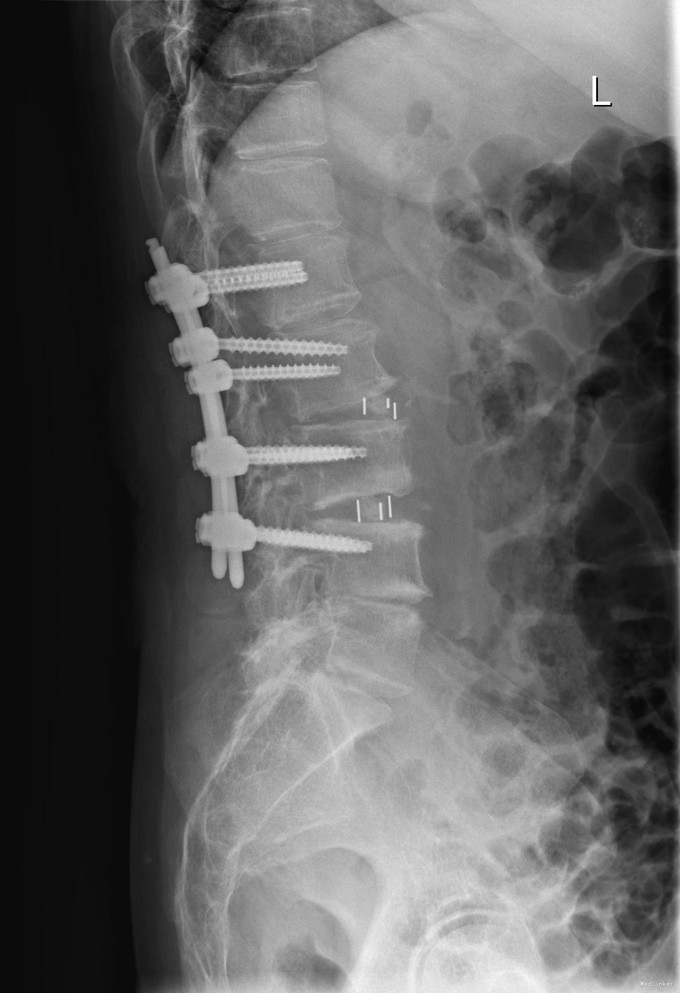

查体:脊柱无明显侧弯,腰背部无压痛,双下肢麻木酸痛,可牵连至脚跟。肌力肌张力可。腰部活动可,前屈后伸时感酸痛,无力。左侧直腿抬高试验阳性。 辅助检查:X线平片:腰椎侧弯前屈,L3椎体轻度滑脱,各椎间隙狭窄,腰椎退行性改变。 MRI:L4-5,L5-S1椎间盘膨出,L2-3,L3-4,L5-S1椎间隙狭窄,S2-3水平骶管内蛛网膜囊肿,腰椎序列不稳定,生理曲度局部后凸。

诊断:1 脊柱侧弯 伴不稳 2椎管狭窄 治疗: 前期微创腰椎侧路融合手术+后期 微创后路经皮内固定

随访:术后1月,患者腰部及腿部酸痛改善,步行良好。